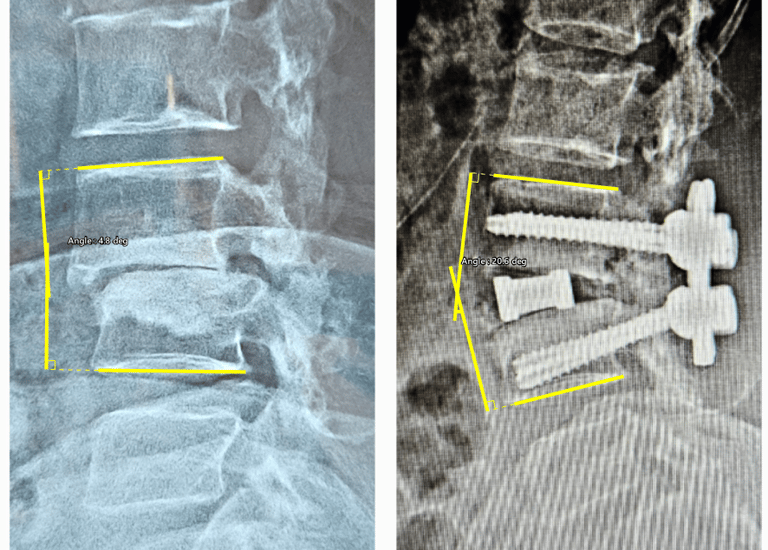

Degenerative Scoliosis Correction

Gentle corrections for lasting posture improvement.

Advanced Lateral Approaches - OLIF

Minimal invasive Spine Solution for maximum outcome.